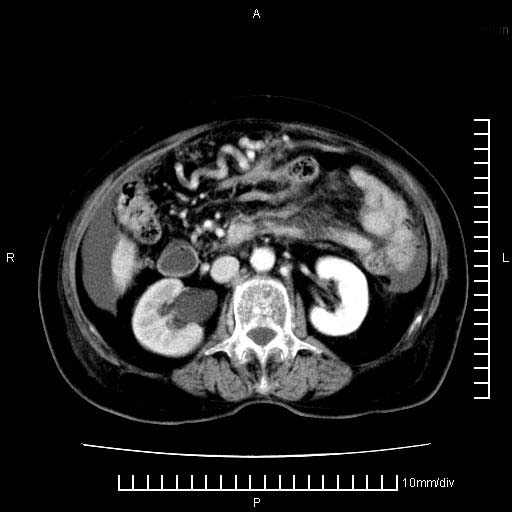

标题: CT28280:腹部增强:女性,80岁

上腹疼痛月余,外院核磁诊断胰腺癌。现临床示右下腹可明显触及包块,可片子上怎么没有看到?

1.胰腺颈体部癌。

2。腹腔积液。

4。右肾盂囊肿。

胰腺体部癌累及周围器官,腹膜、粘连

1。胰腺ca伴腹膜腔转移

2。肝左叶低密度灶,考虑转移可能

胰腺体部癌累及周围器官,腹膜、粘连,临床摸到的可能是粘的组织

胰腺结构模糊,胰尾部见囊性包块,周围脂肪密度增高,左肾前筋膜增厚,胸水、腹水。不符合胰腺ca伴腹膜腔转移。考虑胰腺炎伴假性囊肿形成、胸腹腔积液。

右肾盂囊肿。

1)考虑胰腺癌并胰腺假性囊肿形成。2)肝内低密度灶,不排除转移。3)右肾盂积水。4)腹水。5)右侧胸腔积液并右肺下叶部分膨胀不全。

考虑胰腺ca伴腹膜腔转移、肝左叶转移、右肾积水。右胸腔积液。